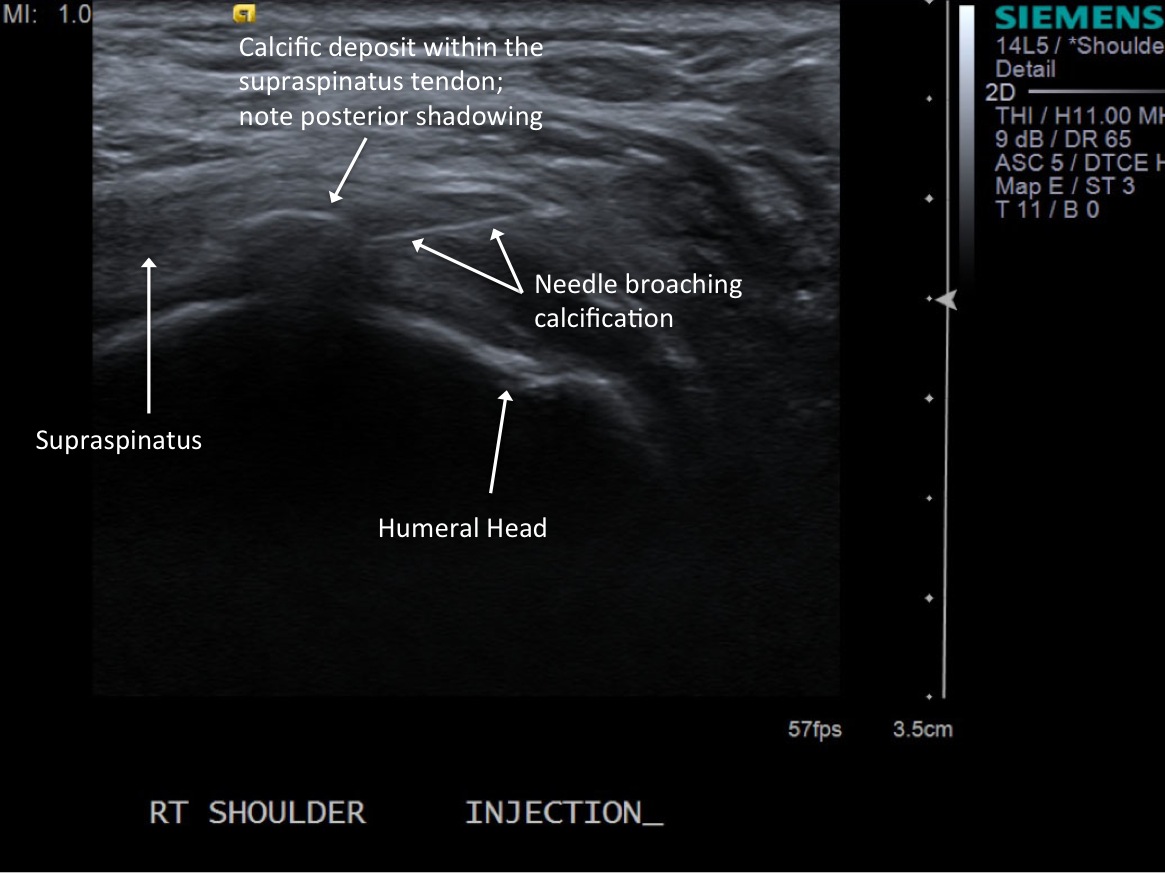

• descriptiondescription

Short axis view of supraspinatus tendon with calcific deposit

• Procedure tray

9.Advance needle under ultrasound guidance to the level of a calcium deposit.